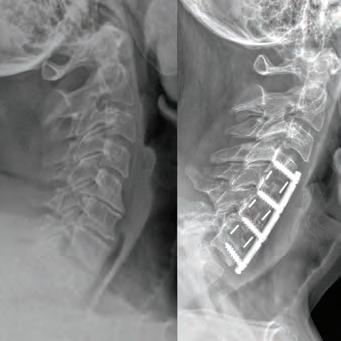

Our cover story this month features Dr. Stephen P. Courtney, a distinguished orthopedic spine surgeon whose commitment to his patients sets him apart in the medical community. Dr. Courtney’s career began humbly, working as an orderly in his teenage years, which sparked his passion for medicine. His academic and professional journey is nothing short of inspiring, having developed innovative spinal care technologies now patented under his name. Dr. Courtney applies a unique blend of hightech and high-touch approaches at Advanced Spine Center, ensuring that every patient receives the personalized care they deserve. Beyond his professional realm, Dr. Courtney is also an avid triathlete, illustrating the deep connection between physical endurance and personal health. Check out his story on page 8.

BOARD-CERTIFIED, FELLOWSHIP-TRAINED ORTHOPEDIC SPINE SURGEON PRACTICING FOR OVER 28 YEARS.

Ths realization inspired Dr. Courtney to design, develop, biomechanically test, complete FDA testing and oversee quality control and validation on a host of tools he created. To date, Dr. Courtney has developed nine spinal product lines and obtained nine patents and 14 trademarks on spine related products.

SURGERY: C4/C5, C5/C6, C6/C7 ACF (ANTERIOR CERVICAL FUSION)